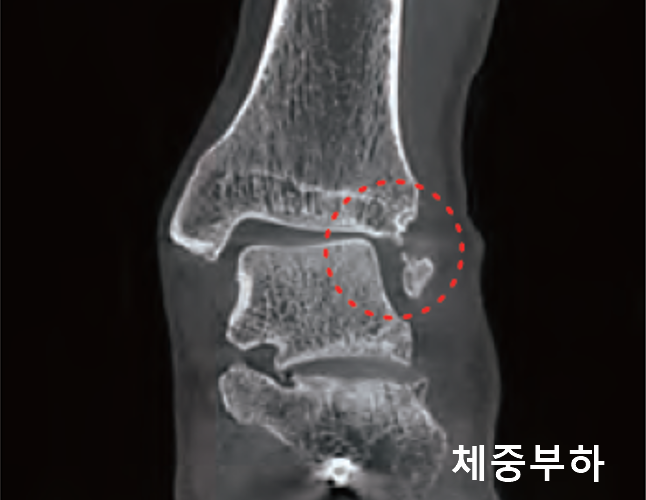

체중이 부하된 상태의 촬영으로 보다 정밀한 진단과 분석

bright WBCT는 체중이 실린 상태에서 촬영함으로써, 비체중부하 상태에서는 확인하기 어려운 다양한 변화를 보다 정확하게 진단하고 평가할 수 있도록 지원합니다.